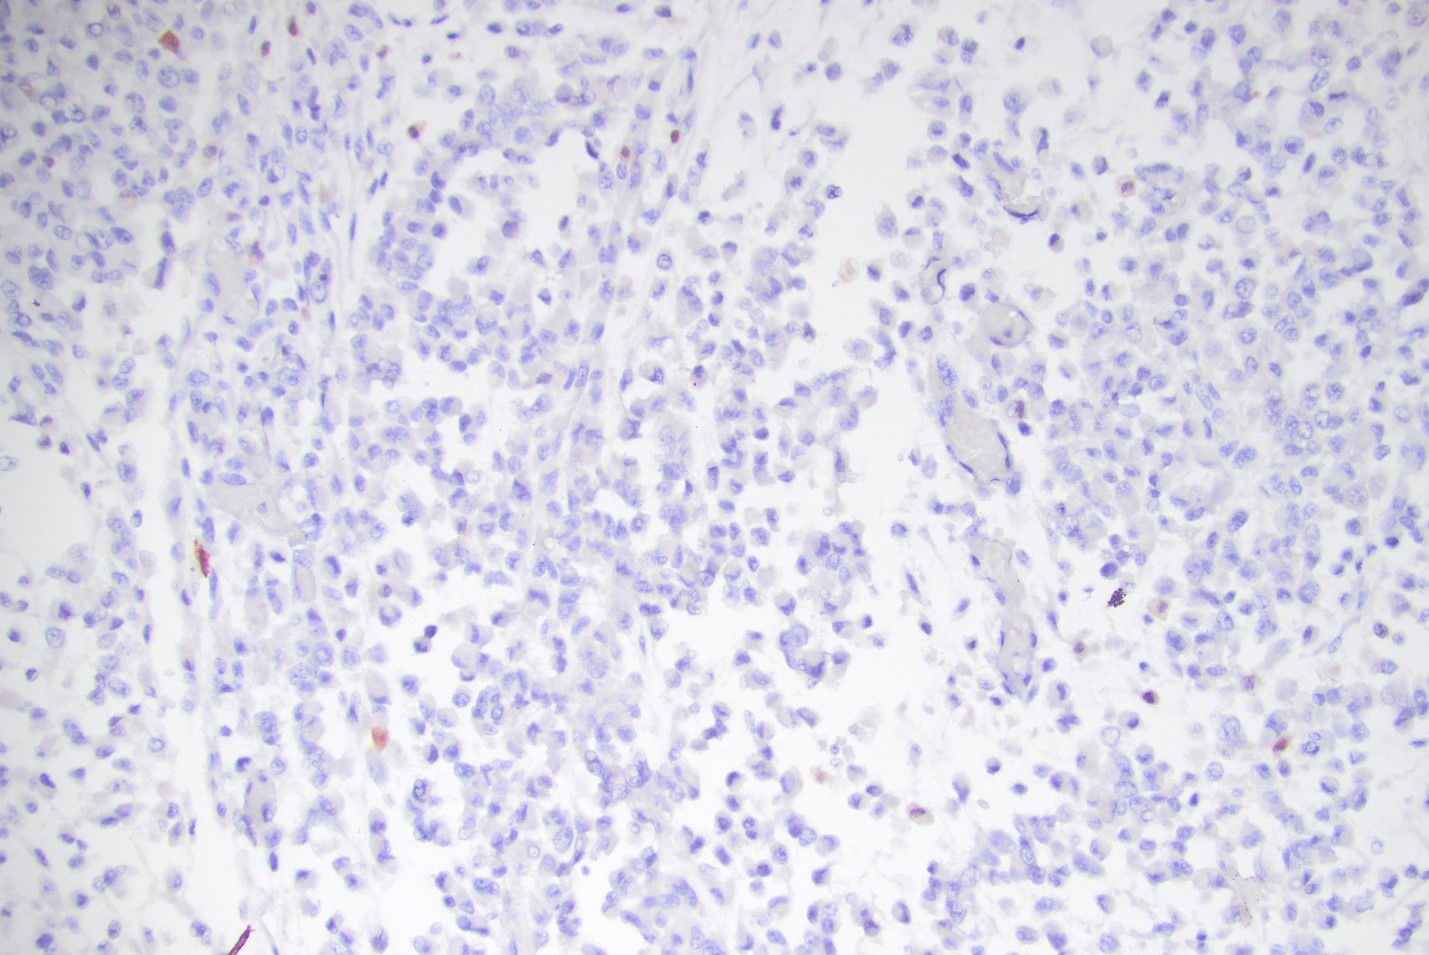

Histological examination of the patient’s pericardial biops­y specimen revealed infiltration by discohesive pleomorphic rhabdoid cells with prominent pink intracytoplasmic inclusions (figures 2-4), vesicular nuclei with prominent nucleoli, and frequent mitotic figures, including atypical forms. The tumor was positive for the cytokeratin cocktail, EMA, and vimentin. Muscle markers (myogenin and myo-D1), S100, and CD30 were negative (figure 5). There was also a loss of INI-1 immunostaining (figure 6). The findings on cytologic evaluation of the patient’s pericardial fluid were congruent with the histologic findings.